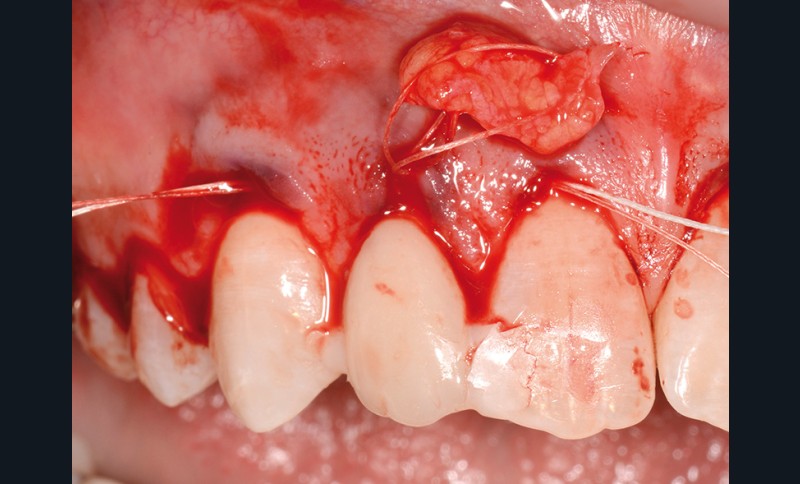

bibli/2.1.11.jpgEtendre les incisions largement au-delà du site receveur ; ici avec le décolleur de papille de Molt (Fabher médical).

bibli/2.1.21.jpgCommencer à décoller en demi-épaisseur avec les lames puis les décolleurs.

bibli/2.2.21.jpgLe décollement doit être très large et aboutir à une laxité maximale.

bibli/rea.jpgSituation en fin d’intervention Deux greffons conjonctifs ont été enfouis par tunnelisation et plaqués par des haubans tractés sur les points de contact.

bibli/2.12.jpgTunnélisation du parodonte superficiel, le tissu doit être lâche, laxe et non déchiré.

bibli/2.12.jpgTunnélisation du parodonte superficiel, le tissu doit être lâche, laxe et non déchiré.